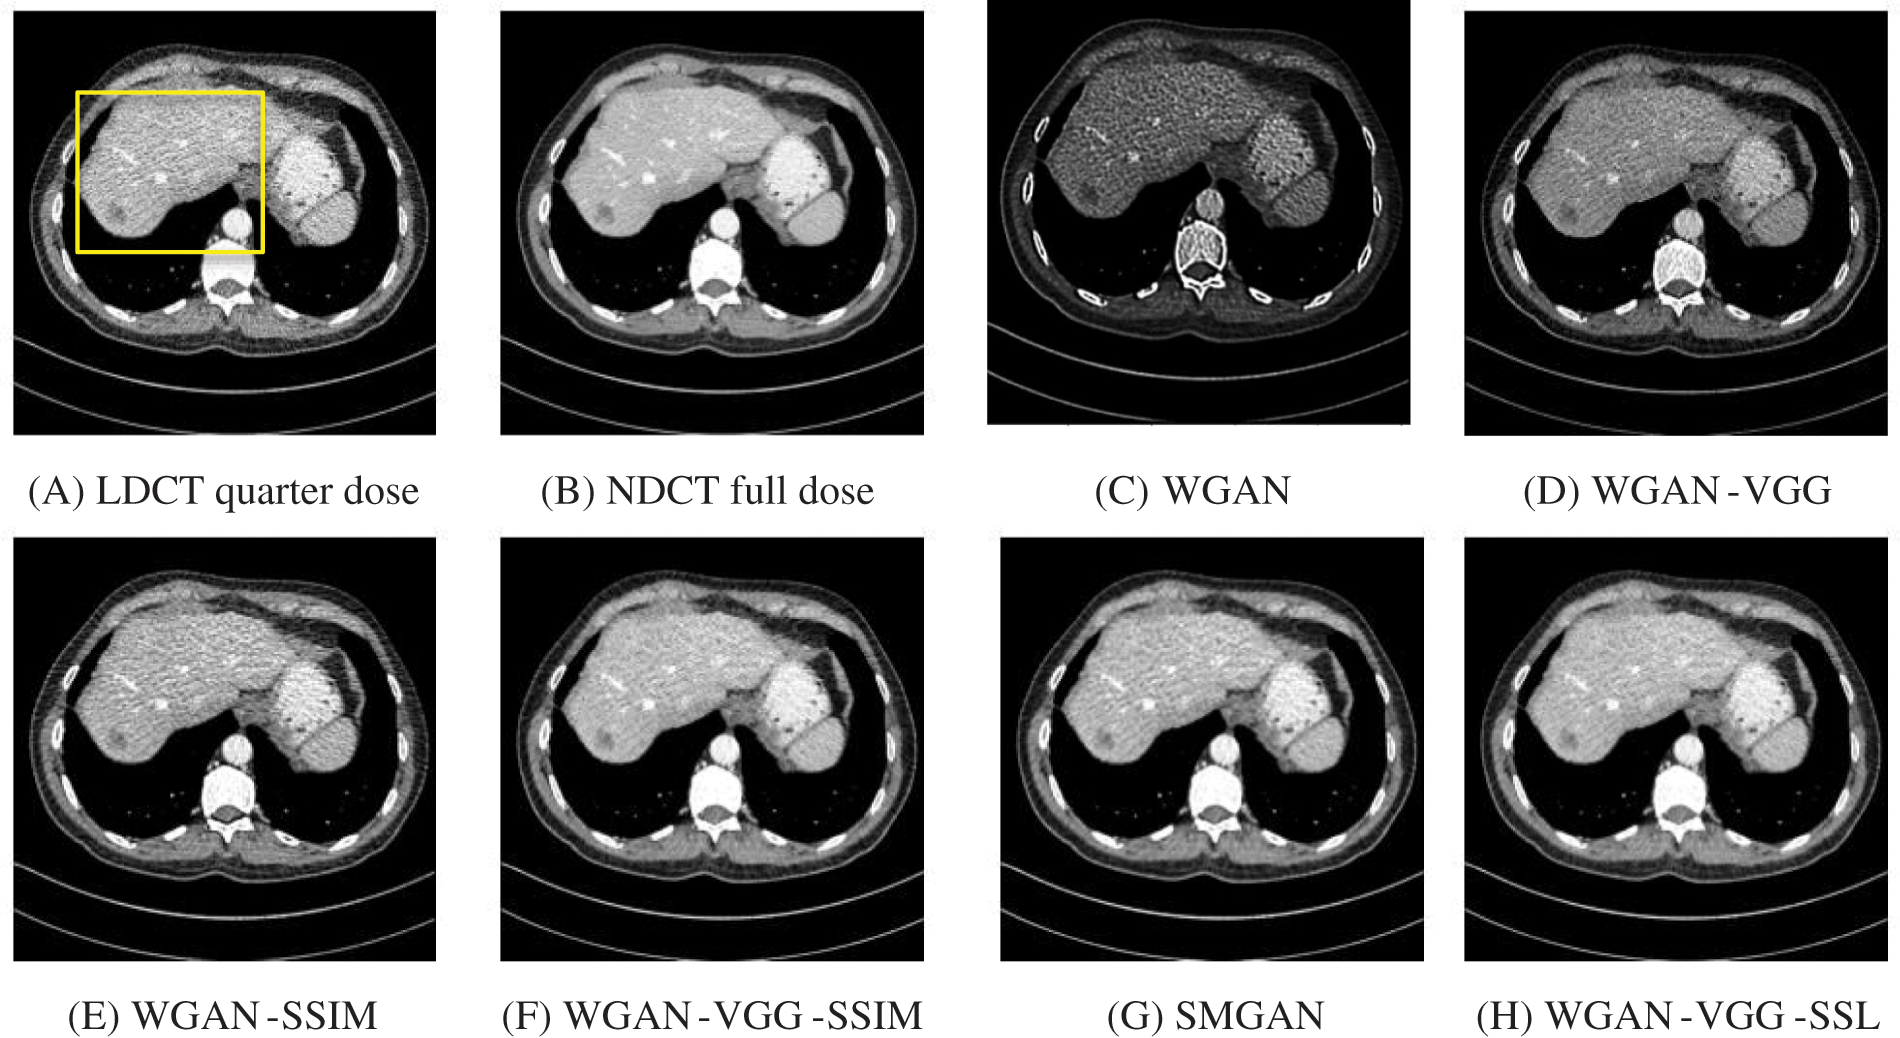

To assess the efficiency of the variant loss function, this work trained the proposed models (WGAN-SSIM, WGAN-VGG-SSIM, WGAN-VGG-SSL), and also trained the best-known models such as WGAN [30], WGAN-VGG [14], and SMGAN [25]. We used two examples of a CT image that were taken from the testing data folders ‘L067’ and ‘L506’, and took a zoomed representative slice of each example to show more structure details as a yellow rectangle in Figs. 2 and 3, and Figs. 6 and 7 respectively. The experimental results showed that generated images using WGAN have a more blurred appearance than the other models. Even though WGAN reduced the white artifact, the produced images are not considerably enhanced compared to NDCT images; some structures are over-smoothed, as shown in Fig. 7C with a red arrow. WGAN cannot preserve the edge details as shown in Figs. 2C and 3C, in which generated images lost the textures of the liver. WGAN-VGG has a few white structures. Although it produced images that were sharper than WGAN, it distorted some of the fine structure details. WGAN-VGG has low contrast as shown in Figs. 2D, 3D, and 7D with a yellow arrow; the performance of WGAN has not improved because it just moves from the noise distribution to the free distribution and does not depend on any human perceptual knowledge. On the other hand, perceptual loss is included in WGAN-VGG. WGAN-SSIM achieved visually better than WGAN and WGAN-VGG and preserved features as marked by the yellow arrow in Figs. 6E and 7E. It is noticed that the three models (WGAN-VGG-SSL, SMGAN, and WGAN-VGG-SSIM) preserved the fine image and retained informative details as shown in Figs. 6F–6H, and 7F–7H by red and yellow arrows. Finally, WGAN-VGG-SSL suppressed noise and artifacts, and generated images that are close to NDCT images; it also kept the structural features better than the other methods and determined the lesion location as pointed out by the red dashed circle in Fig. 6H. In conclusion, WGAN-VGG-SSL achieved better informative feature preservations and visual quality than other WGAN methods.

Figure 2: The generated images from the testing data ‘L067’ on CPU at 2000 iterations

Figure 3: The generated images from the testing data ‘L506’ on CPU at 2000 iterations